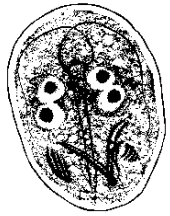

Giardia (lamblia) duodenalis cyst

Giardia (lamblia) duodenalis (cyst)